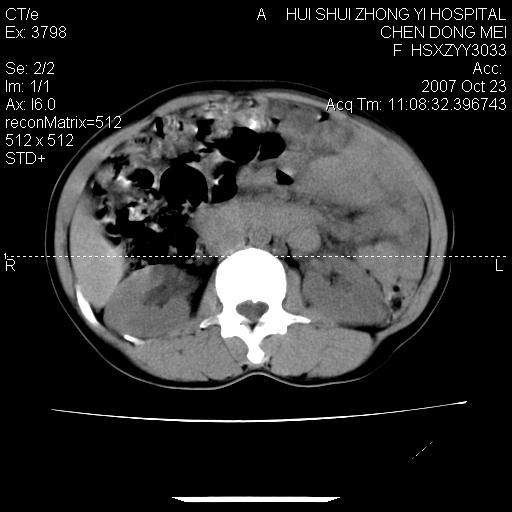

腹腔巨大软组织密度影,边缘光滑,包膜完整,内囊变坏死。腹膜后及盆腔内淋巴结肿大。结合病史考虑卵巢癌可能性大。

病灶内可见脂肪密度影,考虑畸胎瘤可能性大

病变巨大,呈囊实性改变,包膜较厚且完整,内见分膈,周围脏器明显受压移位,病变与左侧附件关系密切,考虑来源左侧附件的囊腺瘤,不除外癌变可能;畸胎瘤可能性较小。

病变巨大,呈囊实性改变,包膜较厚且完整,内见分膈,周围脏器明显受压移位,病变与左侧附件关系密切,考虑来源左侧附件的囊腺瘤,盆腔内见肿大淋巴结,不除外癌变可能。

病变巨大,呈囊实性改变,包膜较厚且完整,内见分膈,周围脏器明显受压移位,病变与左侧附件关系密切,考虑来源左侧附件的囊腺瘤,不除外癌变可能